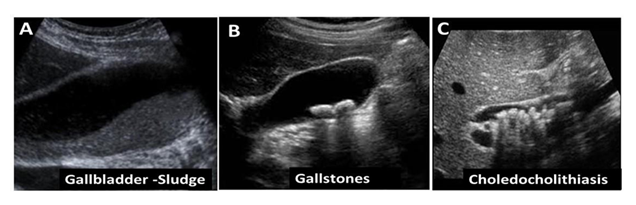

Choledocholithiasis: presence of one or more gallstones in the common bile duct. Ultrasound Images of cholelithiasis appears in Figure 1

In symptomatic disease, depending on the clinical picture and symptoms, an initial laboratory test should be sent in order to investigate the existence of cholestasis or inflammation. Specifically: Complete blood count, ESR, CRP, transaminases, γGT, alkaline phosphatase, total and direct bilirubin, amylase, lipase & urine examination. In simple cholelithiasis, all tests should be normal, however, finding abnormal values may indicate obstruction, inflammation, or both. The diagnosis of the disease is made using ultrasound (Figure 2), an examination with high sensitivity and specificity for its detection, but also capable of giving us other information about possible complications, e.g. cholecystitis, pancreatitis. Other imaging tests such as plain radiography, scintigraphy, and cholangiopancreatography may help in the overall approach or provide complementary information. Plain radiography has no overall role in the detection of cholelithiasis with the exception of calcium carbonate stones, however it can be helpful in the case of ileus from gallstones or the detection of free air sub-diaphragmatically. Scintigraphy after the use of cholecystokinin or a fatty meal may be a useful test for demonstrating gallbladder filling and bile excretion, especially when gallbladder dyskinesia is suspected. In children with complicated cholelithiasis, additional investigation of the anatomy of the biliary tree with magnetic resonance cholangiopancreatography (MRCP) should be performed or endoscopic retrograde cholangiopancreatography (ERCP) which can also be therapeutic by decongesting the bile ducts in case of bile duct stones [28]. ERCP in pediatric patients has similar success and complication rates as in adults, however, ERCP in children should be performed in specialized centers with extensive experience [29].